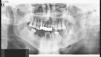

Pruebas complementariasSe realizó una ortopantomografía, que demostró, en el arco mandibular izquierdo, una zona de osteolisis que llegaba a destruir la cortical ósea, así como otros focos radiolúcidos que indicaban una afectación mandibular generalizada (fig. 2)

DiagnósticoOsteonecrosis mandibular por bifosfonatos.